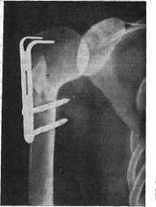

ПРИЛОЖЕНИЕ 9

Аппарат внешней фиксации AO/ASIFпредставлен на

рисунке 9

Рис. 9. Аппарат внешней фиксации AO/ASIF